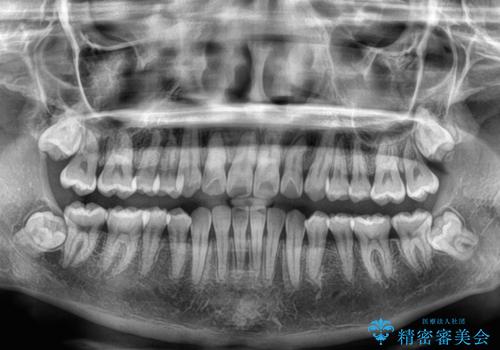

装置の外見を気にしていましたが、短期間で治療を終えることができるだろうと伝えると、安価であるメタルブラケットを選択されました。

想定通り、1年強で綺麗に仕上げることができました。